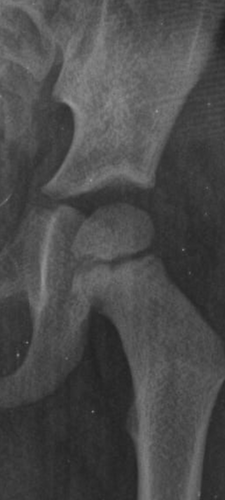

Diversos raios x sem incidência de fraturas ou luxações, porém, com uma lesão na cabeça femoral em formato V, indicando já no raio x a cartilagem soltando devido à necrose e o impacto do osso femoral com o quadril.

No último episódio, o médico plantonista do Pronto Socorro de Balneário Pinhal/RS tentou transferir o Ethan para o Hospital de Tramandaí/RS na área da ortopedia, mas o ortopedista recusou por não ser fratura, mas em conversa com o médico plantonista ele disse que o raio x não estava com um bom resultado e que o diagnóstico dele era “Osteonecrose da Cabeça Femoral”, e que era para ele iniciar imediatamente o uso de cadeira de rodas para o máximo de preservação do osso femoral, pois a osteonecrose da cabeça femoral é quando não há irrigação sanguínea na cabeça do fêmur, então inicia-se a necrose da cabeça do fêmur, levando a dores intensas, desgaste do osso, e que se estiver já gasto (nível 3 ou 4), o único tratamento seria uma cirurgia de prótese.

A suspeita do meu filho inicialmente era Displasia de Quadril, porém recebi já esse diagnóstico na hora com o meu filho nos braços. Agradeci imensamente, pois ao menos dali teríamos uma suspeita sólida, sendo corrigida pelo médico de que era sim o diagnóstico do meu filho e não só um suspeita, por conta das crises e o teste FABER (quando manuseia a perna e descobre onde inicia-se a dor, sendo exatamente entre a junção do fêmur com o quadril), que o ortopedista era experiente na área e que eu precisaria me preparar para uma grande luta pela frente.

Na consulta com o posto de saúde, o médico explicou que a ultrassom era um exame de imagem que mostraria alguns sinais, mas que era necessário uma ressonância magnética para mostrar com nitidez o grau da necrose na cabeça do fêmur para decidir o tratamento, até onde estava necrosado e como está a cabeça do fêmur com detalhes, para verificar se há desgaste e o grau do desgaste ósseo.

O diagnóstico final é apenas uma questão burocrática, e a ressonância é para a definição do grau e as aderências da necrose na cabeça do fêmur, o diagnóstico é mais clínico do que ortopédico, e infelizmente a doença é DEGENERATIVA e NÃO TEM CURA, só a prótese e ele não tem idade indicativa pra fazer porque ainda é criança e está crescendo, se afetar a mobilidade extrema, ele pode fazer a cirurgia de prótese, mas depois terá que trocar conforme cresce, e antes da prótese, serão diversos procedimentos e exames, laudo: